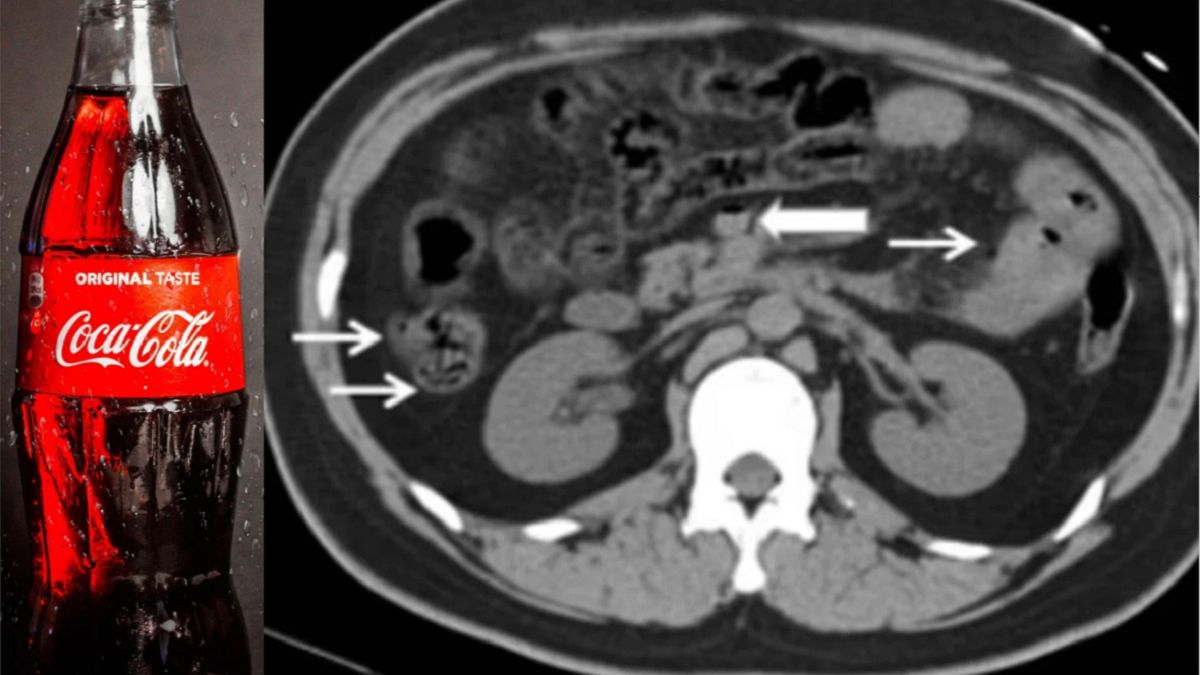

Mężczyzna, który nigdy nie skarżył się na problemy zdrowotne, miał podwyższone tętno, niskie ciśnienie krwi i szybko oddychał. Kolejne badania wykazały, że miał pneumatozę, zbyt dużą obecność gazu w ścianie jelita i żyle wrotnej.

To nie koniec. Miał także niedokrwienie wątroby, zwane również "wątrobą szokową". Jest to rodzaj urazu spowodowanego niskim dopływem tlenu do narządu, co według lekarzy było związane z obecnością gazu w żyle wrotnej.

Główny lekarz Qiang He powiedział, że personel medyczny natychmiast podjął próbę uwolnienia gazu z układu pokarmowego mężczyzny. 22-latek otrzymał również leki, które miały ochronić jego wątrobę i spróbować ustabilizować inne funkcje organizmu przed dalszymi uszkodzeniami.

Po 12 godzinach badania krwi wykazały, że mężczyzna miał poważne uszkodzenie wątroby. Jego stan uległ dalszemu pogorszeniu i zmarł 18 godzin od momentu pojawieniu się w szpitalu.